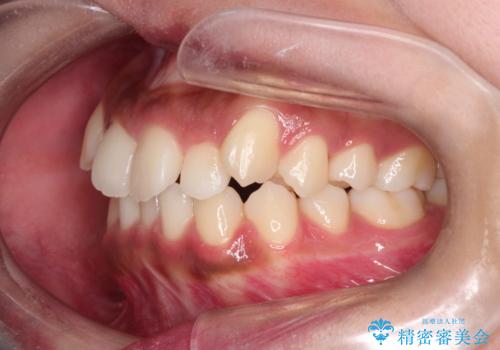

【インビザライン】笑ったときに目立つ八重歯をなおしたい

- 笑ったときに八重歯が見えることを主訴に来院されました。

下の前歯が一本足りない患者様でしたので、シミュレーションを作り、事前に患者様と治療ゴールのイメージをしっかり共有したうえでインビザラインを用いて治療を行っています。

奥歯を後ろのほうに動かすことで、前歯も少し下がることができ、矯正後の口元も満足していただきました。

下顎の前歯が一本ない場合は上下の正中は合いません。